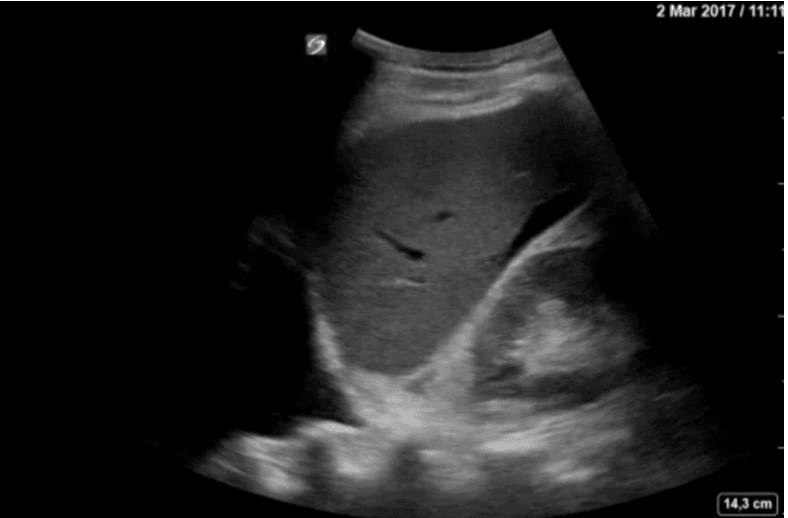

Vous recevez un patient de 23 ans au SAU après un accident de deux-roues (choc du guidon dans l’abdomen).

Il présente une TAS à 90 mmHg, une FR à 24/min, une FC à 128 bpm.

mage d’échographie en noir et blanc.